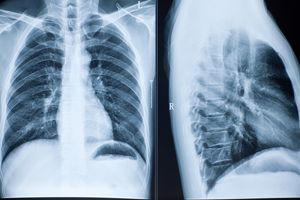

Онкологическая больница Ассута» обладает самым современным медицинским оборудованием, позволяющим произвести обследования, которые определят любой вид рака легких (мелкоклеточный, центральный, периферический, плоскоклеточный и др) на самых ранних его стадиях. К таким видам проведения исследований рака относятся, как новейшие – тонкоигольная аспирационная биопсия, торакоцентез (плевральная пункция), так и традиционные – рентген, низкодозовая спиральная компьютерная томография, бронхоскопия, компьютерная томография, магнито-резонансная томография, позитронно-эмиссионная томография, анализ крови и другие методы точнейшей диагностики заболевания. Все эти методы позволяют точно установить, подтвердить или опровергнуть диагноз этого тяжелейшего заболевания.